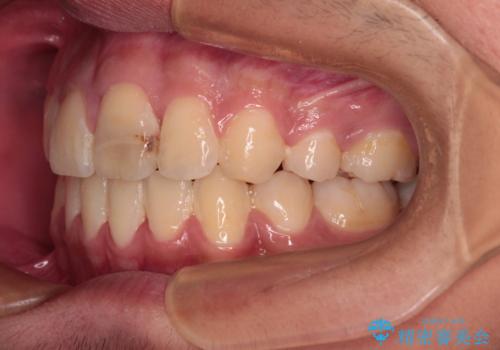

膨らんだ口元 ワイヤー装置での抜歯矯正

- 口元の突出感を気にして来院された患者様です。

上下前歯が著しく前突している状態であったので、上下左右の第1小臼歯4本を抜歯し、ワイヤー装置にて矯正治療を行うこととしました。